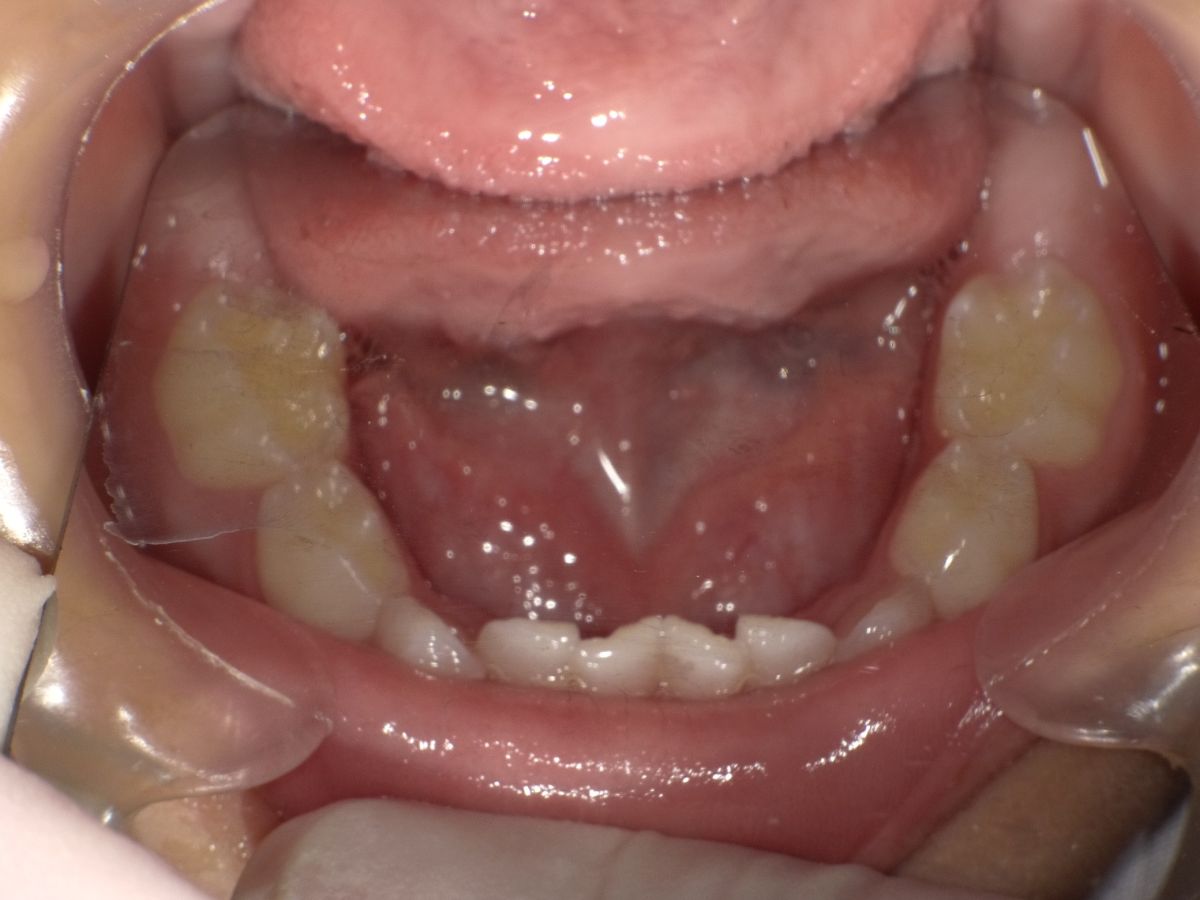

歯並びの叢生(スペースの不足によって、歯が前後に重なってしまう)は、約50年前まではあまり見られなかったが、診療室で約30年前より永久歯に見られるようになり、約10年前より乳歯にも見られるようになってきた。3歳児健診でも、下顎の乳前歯で叢生が見られるようになった。

2022年10月11日公表した厚生科学審議会地域保健健康増進栄養部会 歯科口腔保健の推進に関する専門委員会の報告書によると、歯科口腔保健の推進に関する基本的事項19項目の中で、唯一悪化しているのは「3歳児の不正咬合(叢生)」であった。この原因は、添い乳と食姿勢や食べ方、鼻閉などによる口腔機能発達の仕方にあると推測され、それらを学ぶ機会が重要である。 続きを読む

約50年前まで歯並びの「叢生」はあまり見られなかった。しかし、約30年前から永久歯に見られるようになり、10年ほど前からは3歳児健診でも、下顎の乳前歯で叢生が見られるようになってきた。

保険医協会では、2004年6月の「噛まない子」「噛めない子」の問題提起に始まり、2005年10月からは食育プロジェクトの活動を開始した。陰圧になりやすい飲み物用の狭い口から、いろんな物が食べやすい広い口へ移行せず、歯が内側に傾いたままで口の中も狭く歯がデコボコに生えている。これらの大部分は、乳幼児期の口腔機能発達不全と考えられる。咀嚼の発達は舌の動きと口唇閉鎖が基本となる。「何をどれだけ」食べるかという「栄養素栄養学」から、機能の発達のために「どのようにして」食べるかという視点を持つようになった。 続きを読む

歯並びの叢生は、約50年前まではあまり見られなかったが、診療室で約30年前より永久歯に見られるようになり、約10年前より乳歯にも見られるようになってきた。3歳児健診でも、下顎の乳前歯で叢生が見られるようになった。

厚生科学審議会地域保健健康増進栄養部会 歯科口腔保健の推進に関する専門委員会の報告書によると、歯科口腔保健の推進に関する基本的事項19項目の中で、唯一悪化しているのは「3歳児の不正咬合」であった。この原因は、添い乳と食姿勢や食べ方、鼻閉などによる口腔機能発達の仕方にあると推測され、それらを学ぶ機会が重要である。そして、これを、2024年度から実施予定の次期「健康日本21(第3次)」の重要課題とし、国及び地方公共団体の施策等に反映させるべきである。 続きを読む